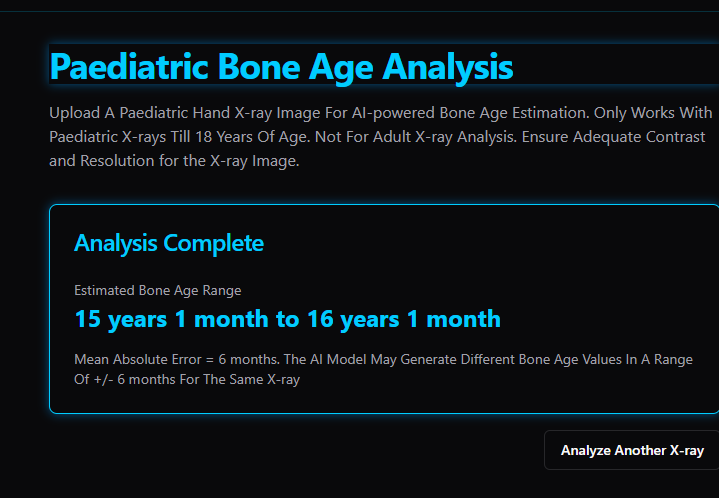

yours are almost fully closed however this ai estimates 15 years 1 month to 16 years 1 month

View attachment 4213468